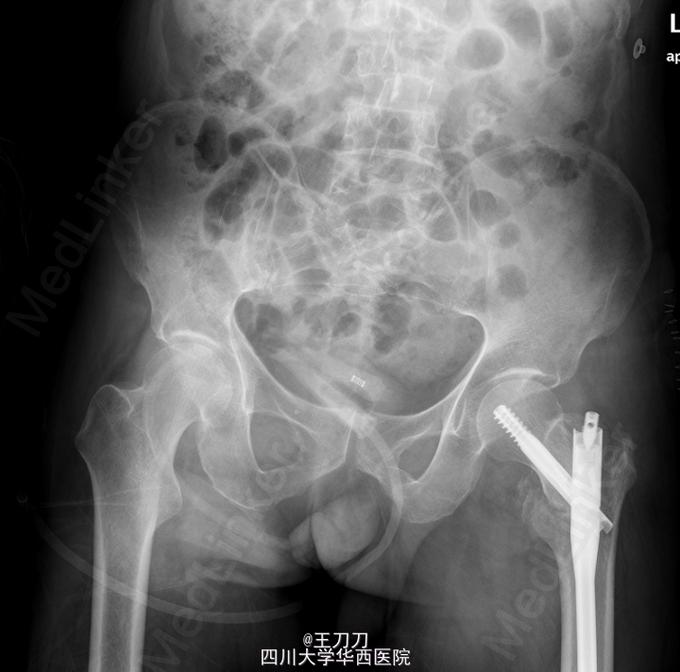

初步诊断:左侧股骨颈骨折. 在全麻下行“左股骨粗隆间骨折闭合复位内固定术”. 取以左股骨大转子顶点向近端延伸切口长约5cm,逐层切开皮肤,皮下组织,纵行分离臀大肌,臀中肌纤维,触及大转子顶点,以大转子顶点前中1/3为进针点,开口,C臂机引导下置入导针至骨折断端以远。扩髓至远侧骨折端,C臂机引导下沿导针进髓内钉至合适深度,连接锁钉支架,套筒定位后切开皮肤约2cm,C臂机引导下以合适前倾角进导针经股骨颈至股骨头前端,C臂机透视见主钉位置良好,打入防旋钉后拧入主钉,拔除导针。以适宜锁定钉行远端孔锁定,取下支架。冲洗,止血,逐层缝合至皮肤,无菌敷料覆盖。